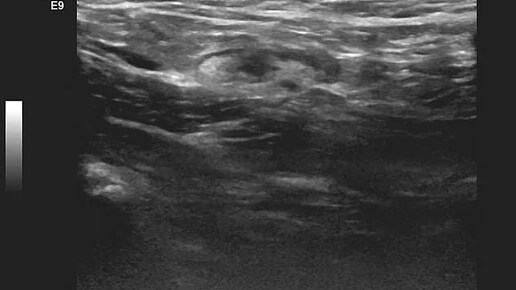

Видео к статье: "Микрометастаз" в лимфатическом узлеhttps://dzen.ru/a/aD_vEeN4BUINS3HY

Ультразвуковые находки от врача УЗД Зорина Я.П.